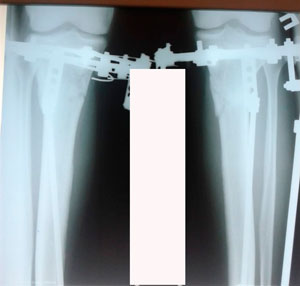

на фиксации

IMG_7674-14-12-19-07-38.JPG

IMG_7673-14-12-19-07-38.JPG